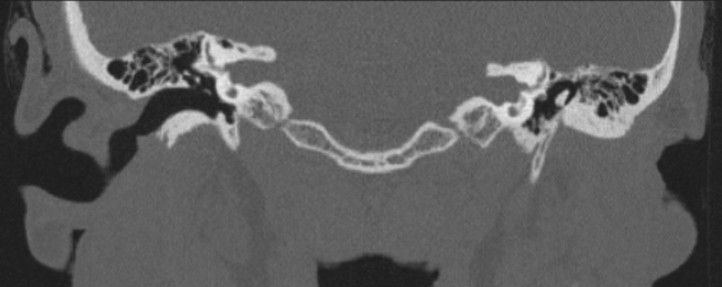

Radiology

- CT: shows temporal bone & middle ear, ossicles, cholesteatoma (squamous epithelium trapped in the middle ear)

- MRI: shows facial nerve (often displaced in middle ear malformations) (Calzolari, 1999 & Carvalho, 1999).

This can be seen in the images below.

Grade III Microtia on the Left - Case courtesy of Assoc Prof Frank Gillard